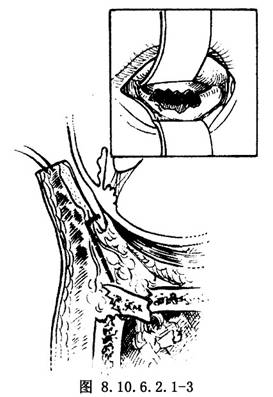

(2)结膜切口:用缝线牵开下睑,沿睑板下缘水平切开结膜,沿眶隔后方剥离结膜至眶缘,水平切开眶缘处骨膜,剥离骨膜暴露骨折区。此切口适用于小而没有眼球运动受限的爆裂性眶底骨折,手术后没有皮肤瘢痕(图8.10.6.2.1-3)。如果破裂较大则应采用皮肤切口。